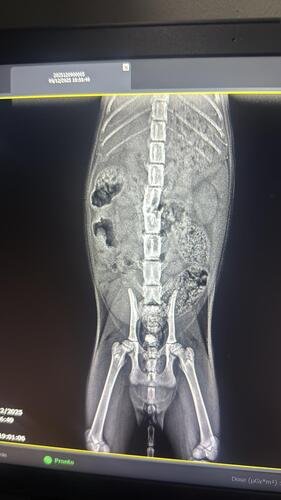

Belinha sofreu um acidente Severo,quebrou a coluna e não consegue mexer as patinhas traseira, precisa ser operada urgentemente.